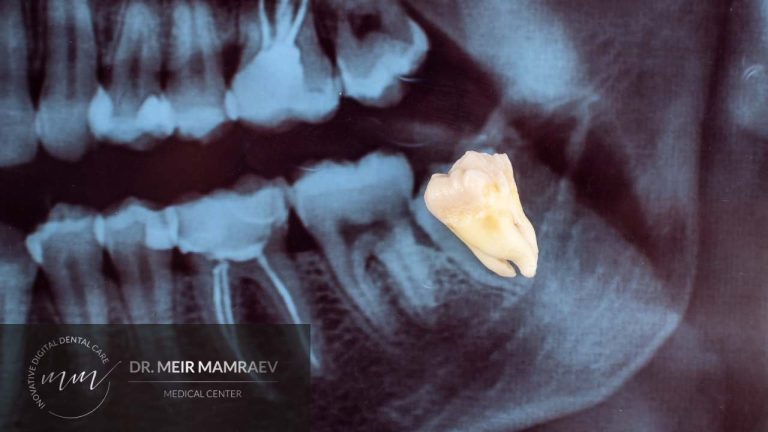

בשלב המתקדם נוצרים כיסים עמוקים בחניכיים, סמוך לשיניים והחיידקים מתחילים לפגוע גם ברקמות העמוקות יותר. במהלך התפתחות המחלה מערכת החיסון מגיבה לנוכחות החיידקים באופן כזה שנוצרת דלקת. כאשר הדלקת כרונית, מתחיל להיווצר הרס נוסף, הדרגתי, של העצם התומכת בשיניים.

"ללא קבלת טיפול, מחלת החניכיים נוטה להחמיר עוד ועוד. עם הזמן, הנזק עלול להביא לנסיגת חניכיים, כאבים עקב שורשים חשופים, התרופפות של השיניים ואף לאובדן מוחלט של שיניים."

ניתוח חניכיים נחשב לאפשרות טיפול שכדאי לשקול ברצינות לאחר שטיפולים שמרניים יותר לא מצליחים להאט או לעצור את התקדמות מחלת החניכיים. הניתוח נחשב לאפשרות ראויה למשל במקרים בהם נוצרו כיסים עמוקים במיוחד בחניכיים או כאשר מאובחן אובדן משמעותי של עצם התומכת בשיניים.

הניתוח מאפשר לרופא להגיע ביתר קלות לשורשי השיניים ולאזורים החולים. כך ניתן להסיר ביסודיות רובד חיידקים ורובד של אבנית. בנוסף, במהלך הניתוח ניתן לטפל ברקמת החניכיים כדי להפחית את עומק הכיסים ולהקל על הניקוי.